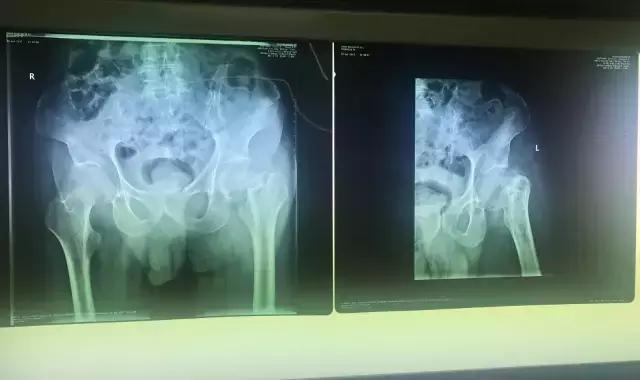

检查结果让老人和家属大吃一惊,原来老人的大胯已经骨折(股骨颈骨折),之前之所以还能勉强站立,是因为老年人对疼痛不是很敏感,再加上陈老先生的忍耐力比较强,所以才没有引起大家的重视。

谈到接下来的治疗方式,家属和医生都犯了难,老人骨折的地方特别特殊,这种股骨颈骨折很难自行愈合,还容易引起股骨头坏死。如果患者年轻一点,同样的病情,医生首先推荐的治疗方式是关节置换手术,因为置换后,患者4-6小时后就可以下床活动,但是鉴于老人毕竟已经92岁高龄,高龄对于手术本身就是一个危险因素,再加上老年患者身体多少有一些脉硬化、冠心病之类的基础病,万一在手术台上发生意外,怎么办?